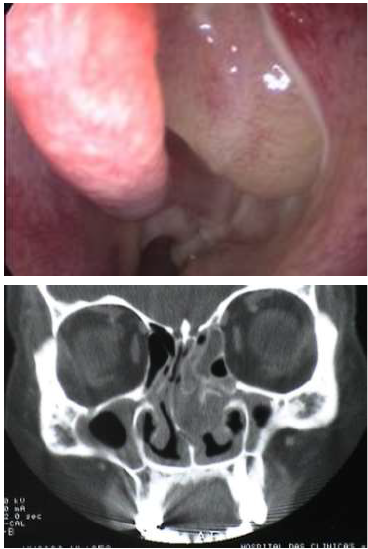

Paciente 38 anos, masculino, vem ao consultório Otorrinolaringológico com queixas de rinosinusites de repetição, obteve melhora acentuada após tratamento para alergia respiratória, porém há 2 meses, após uso de AAS prescrito pelo cardiologista, apresentou exacerbação dos sintomas e, após avaliado clinicamente, foi submetido aos seguintes exames de imagem:

Qual o diagnóstico para este caso: